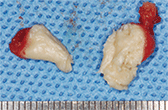

以上の所見から類皮嚢胞と診断し、初診から10ヵ月後に全身麻酔下で嚢胞摘出術を施行した。上顎口腔前庭を切開し鈍的に剥離を進めると、弾性軟で乳白色の病変を認めた。周囲組織との癒着は認めなかった。病変の皮膚側には索状の構造物が上口唇の小孔まで連続していた(図❺)。上口唇小孔周囲の皮膚まで一塊として病変の摘出を行った。内容物はクリーム状で(図❻)、病理診断は汗腺や皮脂腺を有する角化重層扁平上皮に裏装された類皮嚢胞であった(図❼)。

図❻ 摘出物